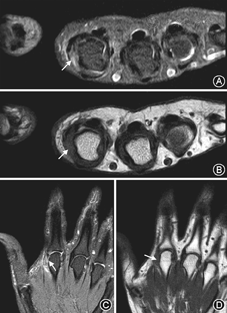

20名正常志愿者的手指肌腱韧带结构在MR图像上均表现为细条状均匀低信号,肌纤维连续(图3)。侧副韧带在冠状位显示最佳;中央束、矢状束、末端腱及屈肌腱在矢状位和轴位显示最佳。

50例手指外伤患者中,侧韧带损伤患者33例,伸肌腱损伤10例,屈肌腱损伤4例。其中有8例在肌腱韧带损伤的同时伴有指骨或掌骨骨折。损伤的韧带及肌腱在T1WI序列表现为肌纤维增粗模糊、部分或完全不连续,PD-FS序列信号不均匀增高,纤维中断,其内可见水样高信号,损伤周围可见软组织水肿(图4,图5)。手指MR影像对比度和信噪比良好,屈伸肌腱和侧副韧带等主要结构显示清晰,可以满足影像诊断的需要。

手指肌腱和韧带在外伤后很容易发生损伤。因此,手外伤患者如要了解骨质情况以除外细微骨折等,应首选X线及CT检查,而临床上怀疑手指肌腱韧带损伤时首选MR检查。MR T1WI序列可清晰显示手指肌腱韧带的正常解剖结构及走行,在T1WI序列中,脂肪呈高信号,肌腱、韧带呈线样低信号,二者形成了良好的对比,更有利于显示正常解剖结构;而PD-FS序列对明确损伤部位、损伤程度及水肿、积液等病变结构更加敏感,更容易发现病变。

通常采用冠状位观察侧韧带的走行,轴位主要观察肌腱形态和覆盖于肌腱上相邻的支持带,以及是否有纵向撕裂或腱鞘积液[5] 。在临床上,最常见的手指侧韧带损伤为拇指掌指关节尺侧副韧带(UCL)损伤,MRI可以精确的根据有无内收肌腱膜的损伤将UCL损伤分为Stener损伤和非Stener损伤两型[6]。当发生伸肌腱和屈肌腱损伤时,通常采用矢状位和轴位观察。MRI可清楚显示矢状束、中央束、末端腱等手指伸肌结构以及伸肌腱和屈肌腱的损伤情况,尤其在急性期临床表现不典型时,矢状面为最佳检测平面[7]。文献报道,利用MRI图像与尸体解剖标本的对照,证实MRI对于伸、屈肌腱撕裂的诊断敏感性为92%,特异性为100%[8]。